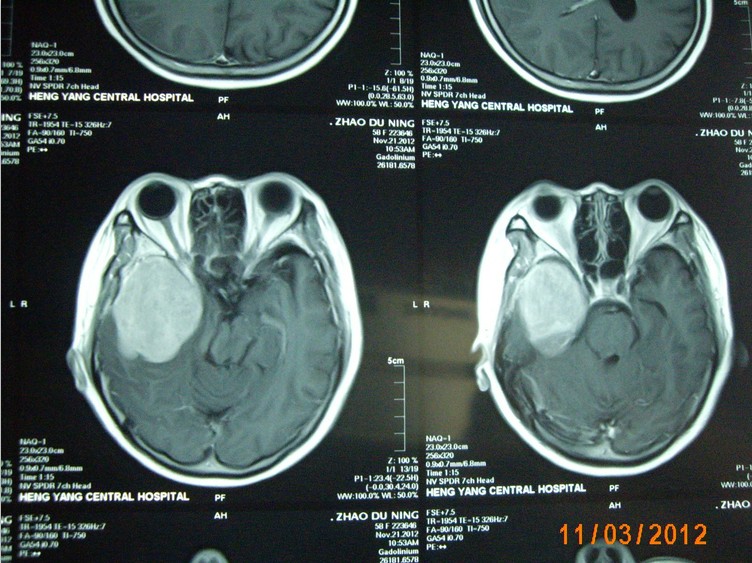

近日,一名來(lái)自常寧的58歲女性患者,因右側(cè)肢體麻木,頭暈3月入住衡陽(yáng)市中心醫(yī)院神經(jīng)外科。頭顱增強(qiáng)磁共振檢查明確右側(cè)中顱窩底巨大腦膜瘤,約10*6*5cm3大小。經(jīng)過(guò)嚴(yán)密的術(shù)前檢查和全科術(shù)前討論,以科室主任鐘三寶主任醫(yī)師為首的手術(shù)組經(jīng)過(guò)4個(gè)小時(shí)的顯微鏡下手術(shù),順利的全切腫瘤。因腫瘤巨大,瘤體切除后局部留下一很大空腔,容易并發(fā)腦組織移位、腦出血,導(dǎo)致嚴(yán)重并發(fā)癥。術(shù)者創(chuàng)新地使用了水囊,逐步減壓等方法,使患者平穩(wěn)地度過(guò)了腦組織復(fù)位關(guān)。術(shù)后未出現(xiàn)任何并發(fā)癥,恢復(fù)良好,順利出院。

(術(shù)后復(fù)查患者恢復(fù)順利)